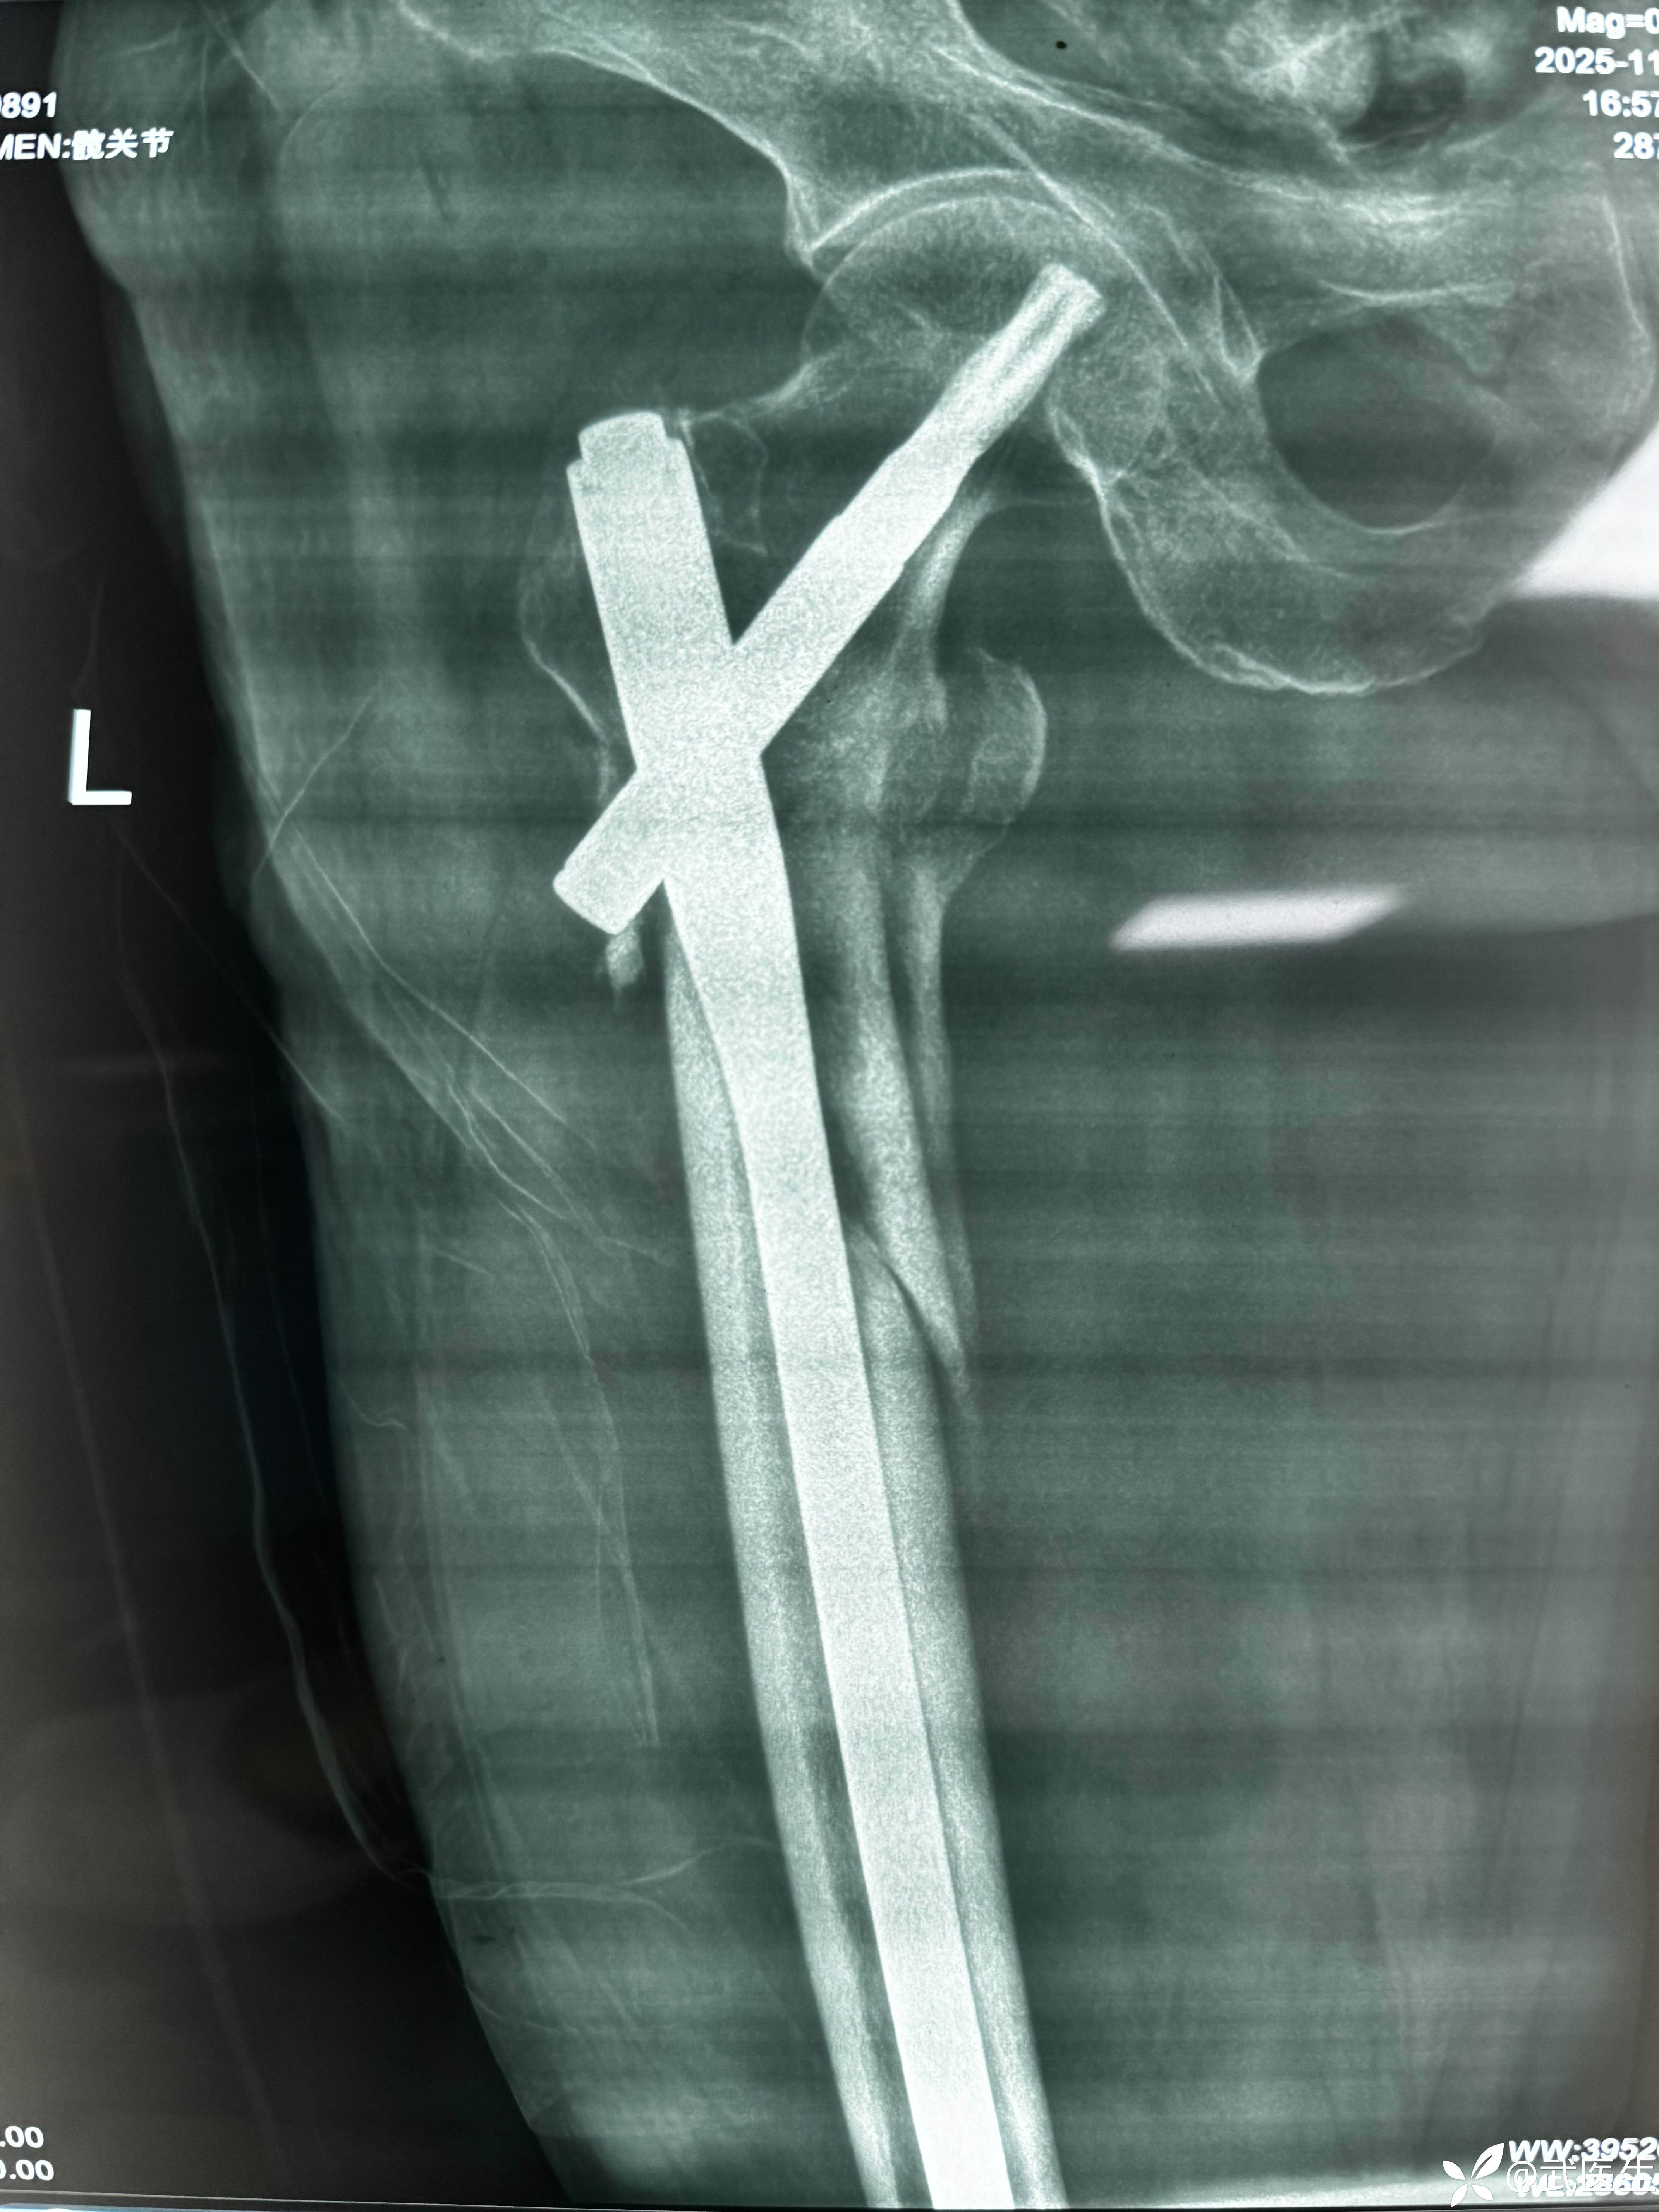

男,70岁,自己摔伤致左大腿疼痛活动受限一小时为主诉就诊,门诊以“左侧股骨近端骨折”为诊断于11月17日收住入院。上图

术后常规手术室拍片,如下

正位,骨折对位良好,头颈钉居中偏下,髓内钉顶天立地。

轴位,呦吼,啥情况,后方这个大尖尖……